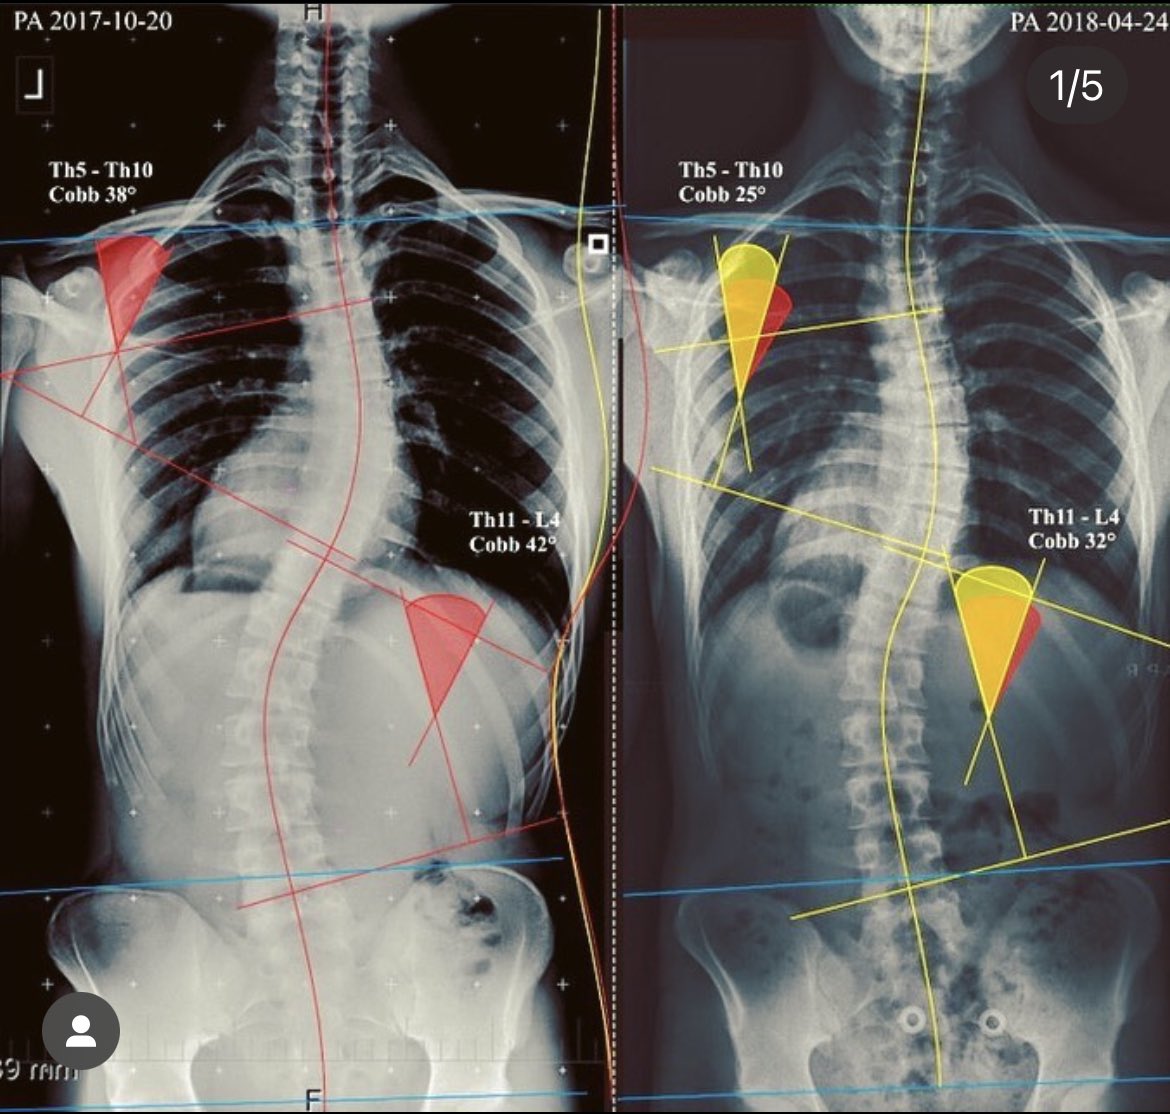

Unique exercise method for spine regeneration using spiral muscle chains treating spinal disorders, scoliosis, disc herniation and many more.

@BBCRadio2 we help to prevent and treat scoliosis non surgical way with exercises. Method developed in the Czech Republic by a medical doctor and available in the UK focusing on treating the cause and not symptoms.